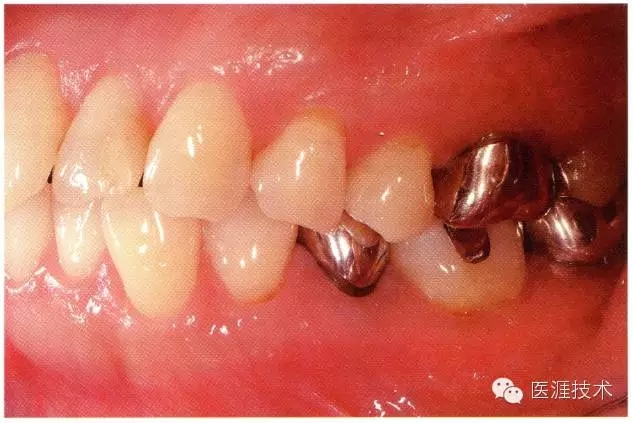

44歲牙周炎女性的臨床照片

640.webp (17).jpg

44歲患有糖尿病病史(未治愈)。菌斑控制不良。通過牙周探診,全頜有4~8mm的牙周袋,在X光片中可以看到上頜前牙處中度牙槽骨吸收,磨牙處重度牙槽骨吸收。二次齲齒和根面齲齒也有發(fā)生。可以看到浮腫性腫脹,收到刺激后會出血。